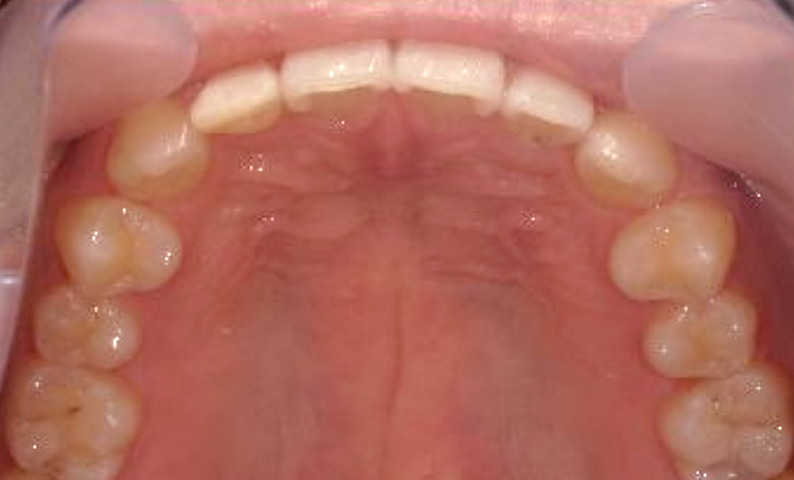

「すきっ歯」を部分矯正で治す!

歯は第一印象にとても重要なパーツです。

そして口元の前歯は特に目立つため、

すきっ歯を治すことで笑顔がより美しくなります。

「部分矯正」とは、歯列矯正の一種で、限られた数の歯や歯列に対してのみ矯正を行う治療法です。気になる前歯だけなど、歯並びに問題がある箇所や、歯並びが口腔内の健康に影響を与えている箇所のみに矯正装置を取り付けます。

部分矯正は症状に応じて治療を行うため、全顎矯正が不要の場合に適しており、治療期間は短く、治療費用も全顎矯正と比べると安く抑えられるため、患者さんの気持ちに寄り添った人気の治療法となっています。